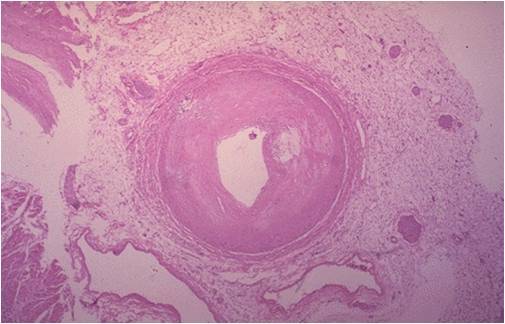

This epicardial coronary artery is almost completely occluded by atherosclerotic plaque. The plaque is heavily lipid laden and has ruptured, releasing thrombogenic substances into the narrow lumen. A thrombus has occluded the tiny lumen that remains.